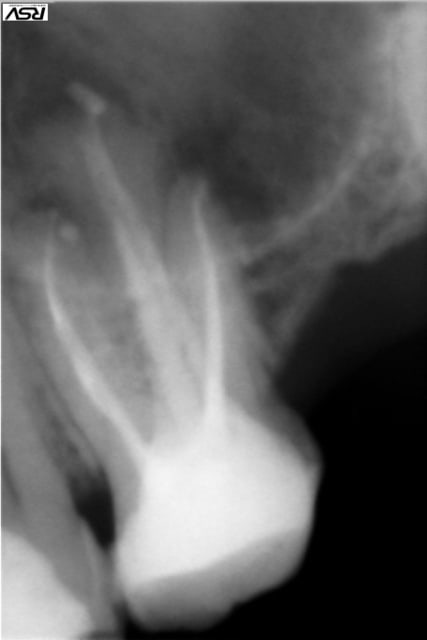

patient se présente pour prothèse remplacant la 11.

je commence par endo sur 22 nécrosee: parage impec edta thermocompactage et AH+.Je donne du birodogyl en préventif.

aorés 2 semaines abcés important avec fistule je prescris de l'augmentin pendant 6j et depuis aucun signe clinique meme pas en palpation mais ....

la radiologie donne une autre chose.

Ensuite, le cône dans la fistule me semble trop fin, j'utilise des cônes de 30/100 pour tracer les trajets fistuleux. Ca permet qu'il soit assez rigide pour bien suivre le trajet, sans faire de boucles sur lui même et aille bien jusqu'à l'origine de la fistule.

Ensuite, 1 abcès après 2 semaines, j'avoue que c'est assez long pour être un abcès réactionnel (donc sans conséquence sur le pronostic). Si le patient ne partait pas, je tenterai quand même une simple surveillance. Mais là, ok pour une chir, mais la résection est indispensable, et l'obturation a retro serait mieux aussi.

j'ai mis toutes les radio pour voir l'evolution de la lésion.

Quand j'ai dit nécrosée j'ai oublié mais peut etre qu'il y avait une fistule ou une réaction apicale légere

S'il n'y a plus aucun signe clinique,pourquoi ne pas revoir cela a son retour de vacances? la dent est bien obturée,il y a un phenomene paro associé,sur la radio on,on croit voir ( je crois voir :))une communication de la lésion avec le ligament,qui a du servir de soupape d'evacuation!

Exact. Sondage paro d'abord. Fracture probable avec perte de l'os alvéolaire vestibulaire.

Dans le cas contraire, vu que le patient part et ne peut pas être surveillé, ne pas s'amuser à refaire une reprise. Chirurgie périapicale AVEC obturation à retro.

Par rapport aux fractures à l'obturation, cela peut arriver mais s'il y a destruction osseuse déjà avancée, la fracture y était avant le traitement, c'est d'ailleurs peut être la cause de la nécrose.

Une chose à faire : sondage en palatin au niveau du cingulum, possibilité de présence d'un sillon palatin.